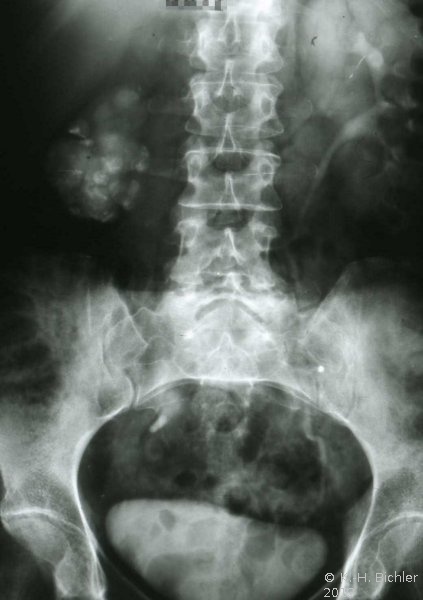

Anfänglich treten nur wenig typische allgemeinentzündliche Symptome auf. Später bestehen entsprechend den entzündlichen Veränderungen in den verschiedenen Organen (Nieren, Harnblase, Prostata, Nebenhoden, Harnröhre) z.B. Brennen beim Wasserlassen (Dysurie) Schmerzen in der Dammgegend, Hoden- und Nebenhodenschwellung, Bakteriurie, Hämaturie und Hämospermie auf.

Häufigste Symptome sind Hämaturie bzw. Dysurie und Schwellung von Hoden und Nebenhoden (z.T. schmerzlos).